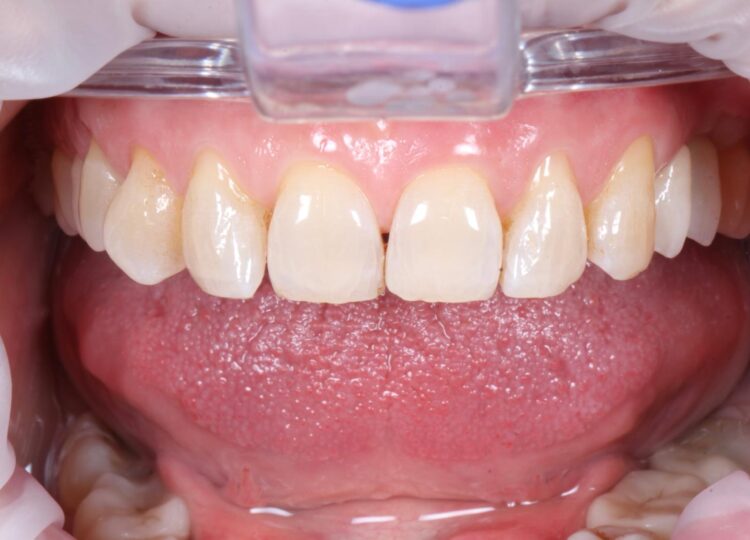

A 58-year-old female patient presented looking to improve the aesthetics and function of her dentition. During a consultation with another clinician, she had been offered conventional implant treatment involving the removal of the UL4 – which had root-filled a retained root – and delayed implant placement. The patient was hesitant to proceed in this way due to the predicted treatment time and expense.

Upon presentation, the initial assessment suggested that an immediate implant may be viable for the UL4 site, alongside simultaneous implant placement in the already healed UL5 site.

A comprehensive clinical assessment was conducted. The patient was generally fit and healthy, was taking no medication, had no allergies and maintained fair oral hygiene. The UL5 site, which had been edentulous for approximately seven years, presented with a substantial depression. This made immediate and simultaneous implant placement even more appropriate for the UL4/5, utilising the bone peaks around the UL4 to create a more favourable UL5 implant position and simultaneous augmentation. Other findings of note were signs of tooth wear on the UL3 and UL6, although these were periodontally sound and completely stable.